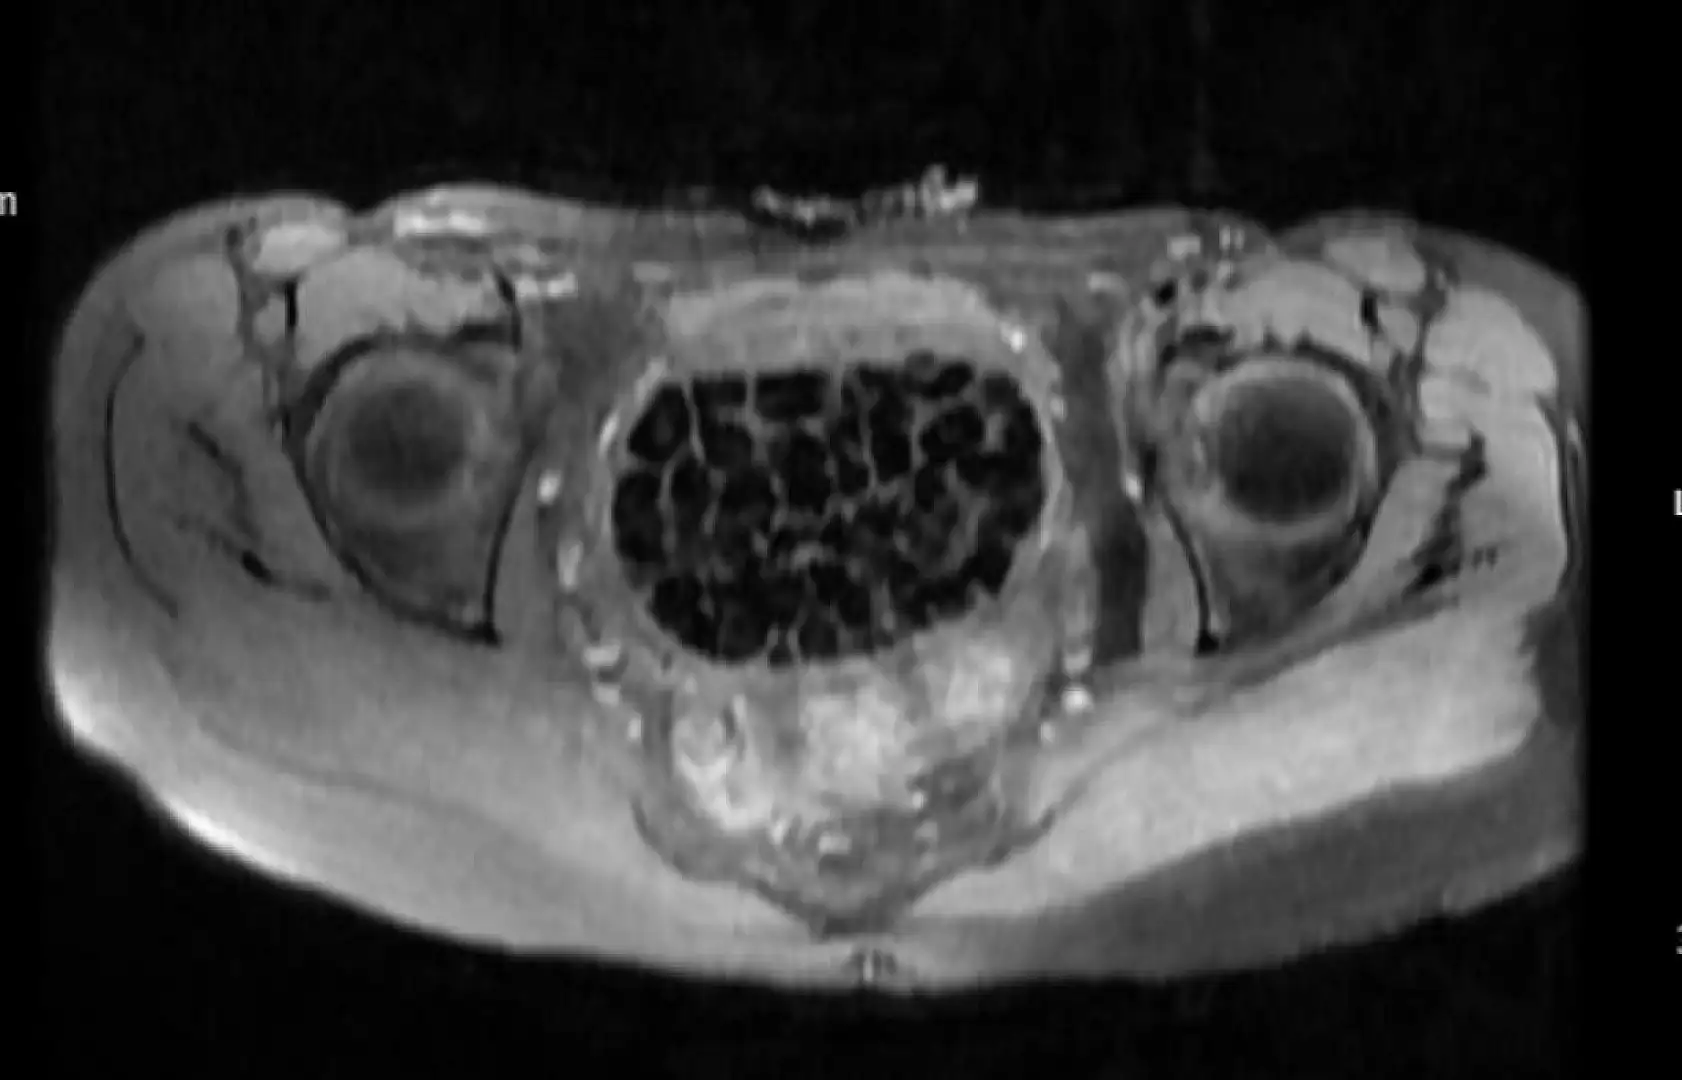

Doğumsal ürolojik hastalıkla dünyaya gelen 21 yaşındaki Fatma Nur Öztürk, şiddetli karın ağrısı şikayetiyle hastaneye gitti, yapılan operasyonla vücudundan 287 adet taş çıkarıldı. Taşlar hem sağlık ekibini hem hasta ve ailesini şok ederken uzmanlar, 'Mesaneden vajene geçtiğimiz esnada tüm vajenin taşlarla dolu olduğunu gördük. Biz de o kadar taş beklemiyorduk, çok şaşırdık, en büyüğü 2,5 santim boyutlarında olan irili ufaklı 287 taş. Literatürde çok nadir görülen bir olay' derken hasta Öztürk, 'Ağlatacak dereceye getiren ağrılardı. 287 taş denince çok şaşırdık, çakıl taşı resmen. Şu an kendimi çok iyi hissediyorum' dedi.

Hastalık ve tanı sürecine ilişkin bilgi veren Op. Dr. Dönmez sözlerine şöyle devam etti: "Konjental anomali, bunu gebelik esnasında yapmış olduğumuz ultrasongrafi muayenelerinde saptayabiliyoruz. Normalde mesanede idrar birikmesi gerekirken biz ultrasonda bu bebeklerin mesanesinde birikmediğini görüyoruz. Oradan tanıya gidebiliyoruz. Önemli olan burada tanıyı koyduktan sonra bu hastaların 3’üncü düzey, multidisipliner bir hastanede doğum yapmasını sağlamak. Doğumdan sonra en kısa sürede mesane rekonstrüksiyonunun multidisipliner ekiplerle gerçekleştirilmesini sağlamak çünkü mesane direkt karın dışına açıldığı için enfeksiyona açık bir ortam oluşuyor. Bebeğin hayatını tehdit edecek ciddi enfeksiyonlar gelişebiliyor. Anomalilerin durumuna göre bu hastalar bir sıra ameliyat geçirerek sağlıklı bir şekilde hayatlarına devam edebiliyor. Hastamızı muayenelerine, kontrollerine çağıracağız. Biz de o kadar taş beklemiyorduk, maksimum 100-110 kadar bir taş vardır diye bir düşüncemiz vardı, sayalım dedik. 287 taş da bizi ameliyat esnasında heyecanlandırmıştı. Saydıktan sonra bu bilgiyi hastamız ve ailesiyle paylaştık. Onlar da şaşkınlık halindeydi, böbrek taşını düşüren bir kişiyle konuştuğunuz zaman bir taşın bile ne kadar zor bir şekilde düştüğünü size tarif edecektir. Taşların uzun yıllar boyunca yavaş yavaş oluştuğunu düşünüyoruz."